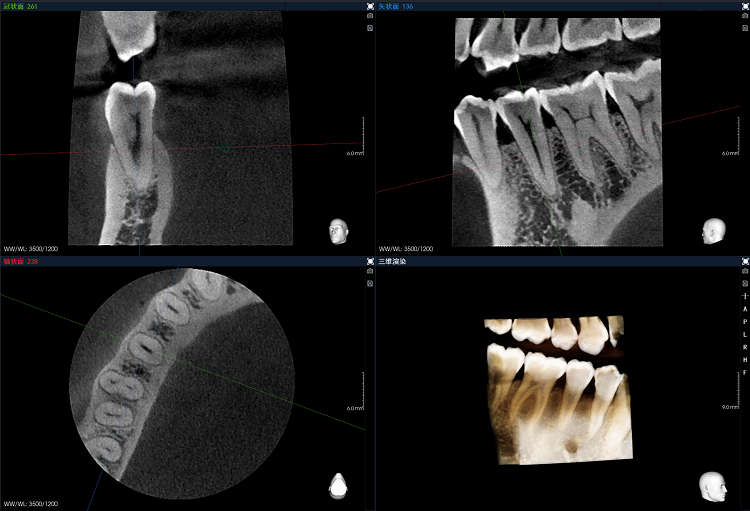

4x4cm高清局部成像,最小重建體素50μm,細微病灶分毫畢現(xiàn),牙體牙髓診療更方便。

4、極致影像――去偽存真,分毫畢現(xiàn)

全新一代Bon準能譜偽影校正技術,去偽存真,種植體影像更清晰。